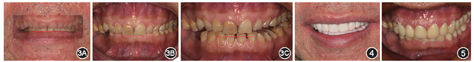

面部左右基本对称,上唇长度适中,微笑时上前牙显露量不足;面高︰面宽=1.26;侧面观下颌后缩,凸面型,面下1/3高度减小(图1A)。

面像;E:下颌

面像

面像双侧关节区、颞区、下颌角区未查及压痛;开口度三横指半;开口型直线型;双侧关节区未闻及弹响。

上颌中线正,下颌中线右偏1 mm,11、12变色;15—17、32—42过萌,上下前牙变短,后牙区

面磨耗;45—47缺失;上颌拥挤度3.5 mm,下颌散在间隙5.0 mm;施佩曲线曲度3.0 mm;上下前牙Bolton比76.3%;牙龈缘稍红肿(图1B,图1C,图1D,图1E)。